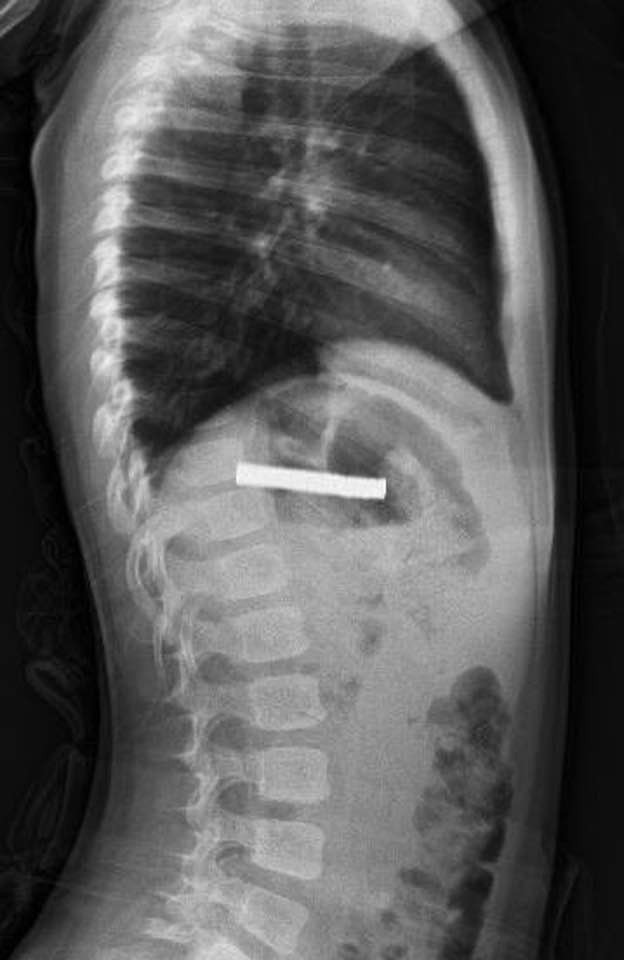

Daha sonra çocuk Elazığ’a sevk edildi. Fırat Üniversitesi Çocuk Gastroenteroloji Hepatoloji ve Beslenme Bilim Dalı Başkanı Prof. Dr. Yaşar Doğan, çocuk hastanın yemek borusuna yapışmış 19 mıknatısı endoskopik yöntemle çıkardı.

Mıknatıslar uzun süre yemek borusunda takılı kaldığı için yemek borusu ve mide girişinde zedelenmeler olurken, çocuğun sağlık durumunun iyi olduğu ve taburcu edildiği öğrenildi.